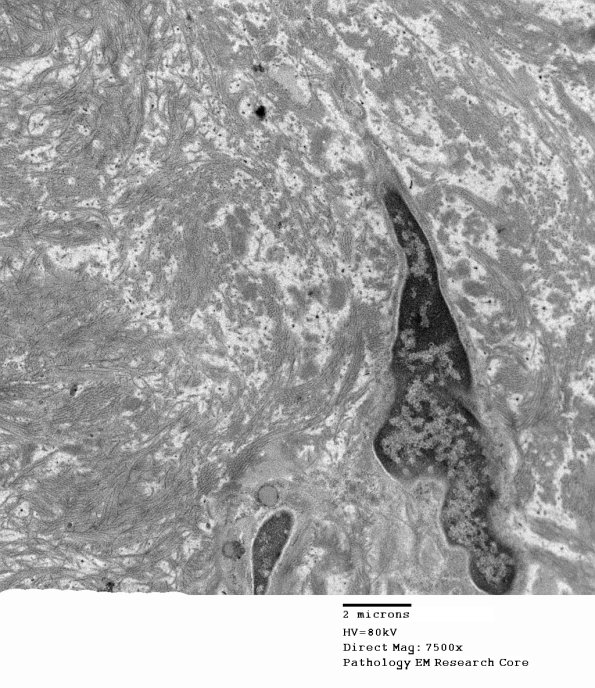

Two magnifications of a structure that resembles a Renaut body which is overrun with collagen and oxytalan. (Electron micrographs)